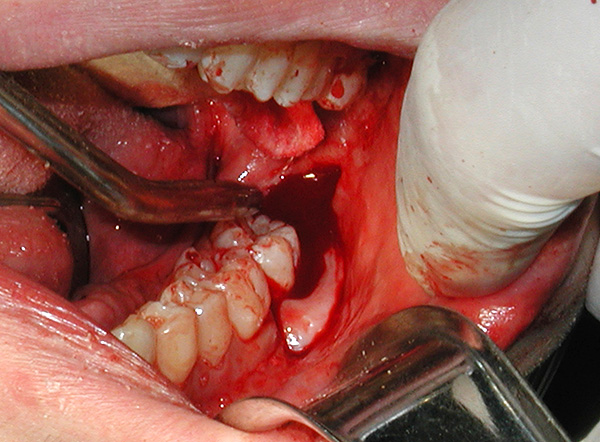

- Creazione dell'accesso al dente retinato (incisione della gomma con un bisturi, rimozione del tessuto osseo con taglierine con raffreddamento. In alcune cliniche possono utilizzare un bisturi laser);

- Estrazione di un dente del giudizio da parte degli elevatori o segatura con frese in parti e eliminazione graduale di ogni pezzo. Non aver paura di tagliare un dente dalla mascella, poiché accelera quasi sempre il lavoro 2-3 volte e ti consente di ottenere un risultato positivo in meno tempo. Rispetto alla segatura, è molto più spiacevole scavare un dente retinato con uno scalpello;

- Emostasi (arresto del sanguinamento). Dopo la rimozione, dopo la rimozione possono essere inseriti nel foro preparati a base di osso artificiale (plastica avvolta), una spugna emostatica o turunda con agenti antinfiammatori, analgesici e antisettici.